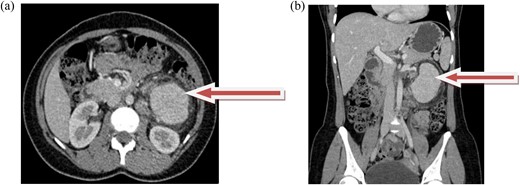

Contrast-enhanced CT revealed an 8 × 5.4 × 5.4 cm, well-defined, intensely enhancing retroperitoneal mass anterior to the left kidney, with an arterial supply from the left second and third lumbar arteries. Marked soft tissue stranding suggested a neurogenic tumor, likely an extra-adrenal pheochromocytoma or paraganglioma (Fig. 1a and b). A core biopsy from another center also suggested paraganglioma.

(a and b) axial and coronal computed tomographic scans, respectively, show intensely enhancing round to oval soft tissue density mass in the left retroperitoneal area anterior to the left kidney.